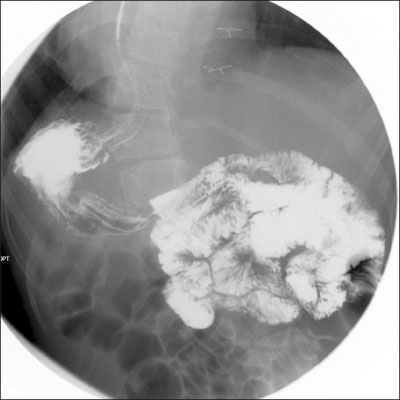

The patient experienced recurrent aspiration pneumonia and seizure one year ago. There was no problem in ingestion until aspiration pneumonia occurred, but, because of increased aspiration tendency during oral feeding, he was under nasogastric tube feeding for 1-year. For long-term management, percutaneous endoscopic gastrostomy (PEG) was planned, and an upper gastrointestinal (UGI) study was done in our institution. On UGI, the right-sided stomach was seen, and associated intestinal malrotation, without volvulus, was found (

Fig. 1). Situs anomaly was suspected for the first time since birth during this study, and PEG was performed without complications when he was 17 years old.

Fig. 1Right-sided stomach suspecting situs anomaly in upper gastrointestinal series.